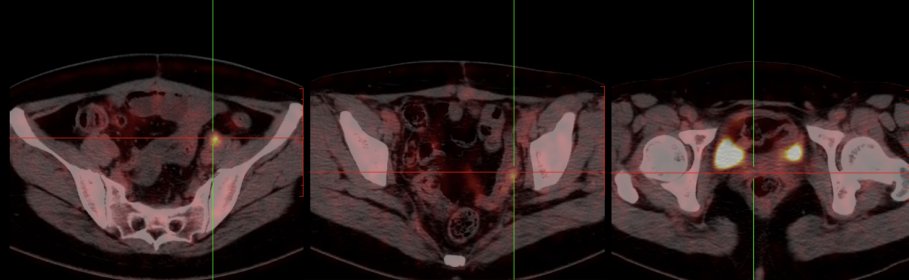

PET-CT: 1、①卵巢癌术后,子宫及双附件缺如,阴道残端未见明确肿瘤征象。②肝S7段包膜下稍低密度灶,FDG代谢增高,考虑转移。③左侧髂外血管旁肿大淋巴结,FDG代谢增高,转移可能大。④左侧盆底(乙状结肠左旁)结节伴高代谢,倾向转移灶。2、双侧筛窦及左侧上颌窦炎。双侧扁桃体区对称性FDG代谢增高,考虑炎性增生。3、右肺上叶前段结节,FDG代谢未见明显异常增高,倾向炎性病变。双肺多发小增殖灶。4、肝内多发囊肿。 5、双侧肾上腺结节,考虑腺瘤。6、腹膜后、双侧腹股沟多发增大淋巴结,炎性增生可能性大。

PET-CT(2022年11月1日):对比2022年1月6日PET-CT,1、①卵巢癌术后改变,阴道残端未见明确肿瘤征象,较前相仿;②盆底腹膜、左下腹膜局部明显增厚伴FDG代谢增高,FDG代谢增高,较前新发,考虑转移;③肝脏术后改变考虑,局部少量积液;④右侧心膈角肿大淋巴结伴FDG代谢增高,较前新发,考虑转移;⑤肠系膜间隙、结肠旁及腹膜后多发淋巴结,部分FDG代谢略增高,较前相仿。2、左侧筛窦及左侧上颌窦炎。双侧扁桃体炎。3、右肺上叶前段结节,FDG代谢未见明显异常增高,较前相仿,倾向炎性病变。4、肝内多发囊肿,较前相仿。肝右叶钙化灶。5、右侧肾上腺显示欠清,左侧肾上腺略增生,较前大致相仿。6、双侧腹股沟多发炎性增生淋巴结,较前相仿。